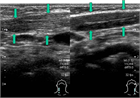

1. 乳児期に認められる頚部腫瘤が、エコー上胸鎖乳突筋の腫脹として捉えられ、正常の筋に認められる層状の筋内部エコー像に乱れが生じている場合には、筋性斜頚と診断する。

1. 一般に筋性斜頚は乳児期に診断されるが、その時期に診断されずに年長で斜頚位を呈している場合には、ときとして診断に難渋することがある。こういった場合には、胸鎖乳突筋の拘縮を触知できない場合でもエコー像では左右差を認めることが多く、診断に有用である。